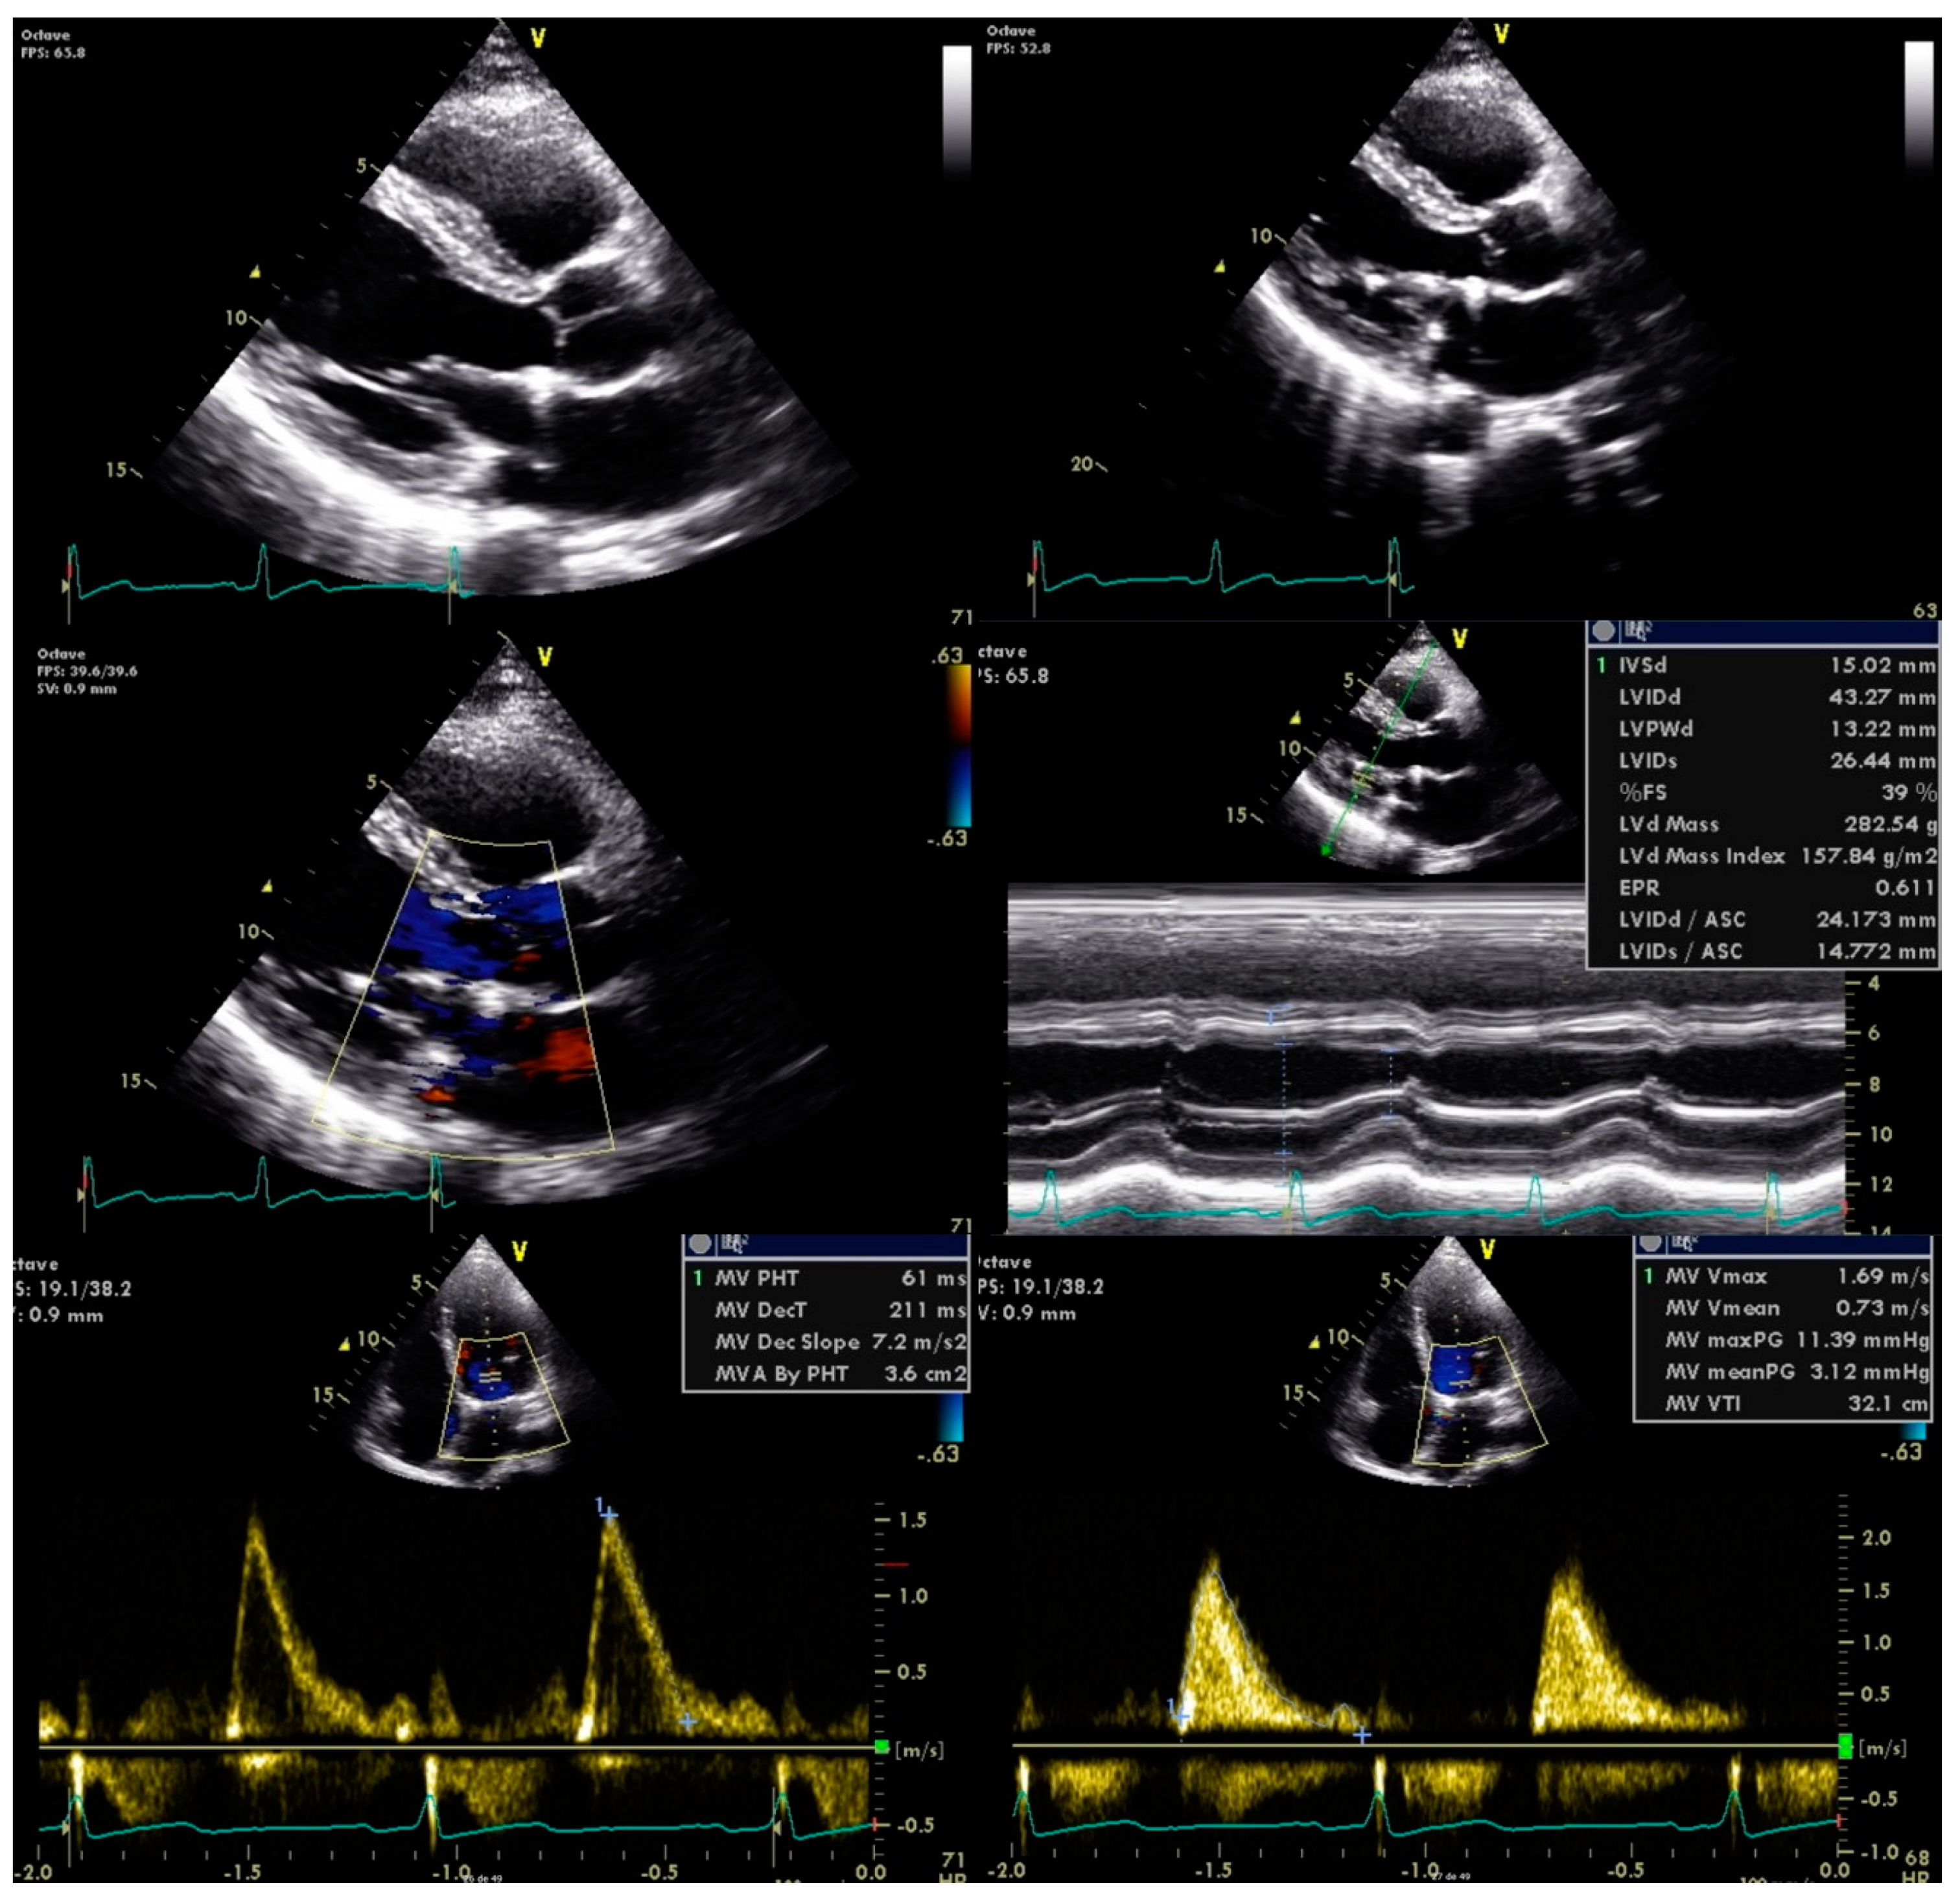

Antimicrobial therapy was promptly initiated with vancomycin and gentamicin for six weeks. He was also referred to the cardiothoracic surgery department for mitral valve plasty, with no further complications observed (Figure 3).

Figure 3. Transthoracic echocardiography post mitral valve plasty.